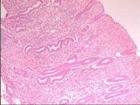

CT導向細針抽吸活組織檢查常用的活檢方法有五種:①穿刺抽吸活檢:適用於具有一定體積,表面有正常組織覆蓋的實性腫瘤。臨床多用空注射器刺入瘤體,然後回抽注射器芯,造成負壓,將瘤組織碎屑吸入空針內,將此微量組織塗於載玻片上,經細胞室醫生進行固定、染色等處理,在顯微鏡下觀察作出診斷。其操作簡便、安全、無需麻醉,對惡性腫瘤的診斷符合率達80%以上。②鉗取活檢:用活檢鉗咬取小塊瘤組織,進行病檢。適用於暴露於體外的腫瘤或器械(如內鏡)可觸到的腫瘤。③切取活檢:指通過手術切取部分腫瘤組織進行檢查。其適用面廣,但因病灶多有殘留,創面周圍難免污染,理論上可增加腫瘤轉移的機會,故目前臨床套用較少。④切除活檢:指將腫物全部切除後進行病理檢查的方法。⑤冰凍活檢:又稱快速病檢。

常規的病理檢查是將待檢組織用液態石蠟包埋,固定後用切片機切成很薄的片,染色後再進行顯微鏡觀察,全過程約需3天。而有些腫瘤因手術中難以確定性質,無法確定手術切除範圍,這時就需做冰凍活檢。冰凍活檢是利用特殊設備將腫瘤組織速凍切片、染色、鏡檢,全過程僅需半小時。臨床醫生可根據病理結果,選擇適宜的治療方案。